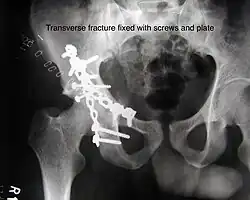

Transverse fracture showing upper iliac fragment, lower ischial and pubic fragment -

Transverse fracture fixed with screws and plate

The final management depends on the size of the fragment(s), stability and congruence of the joint. In some cases traction for six to eight weeks may be the only treatment required; however, surgical fixation using screw(s) and plate(s) may be required if the injury is more complex. The latter treatment will be called for if bone fragments do not fall into place, or if they are found in the joint, or if the joint itself is unstable.